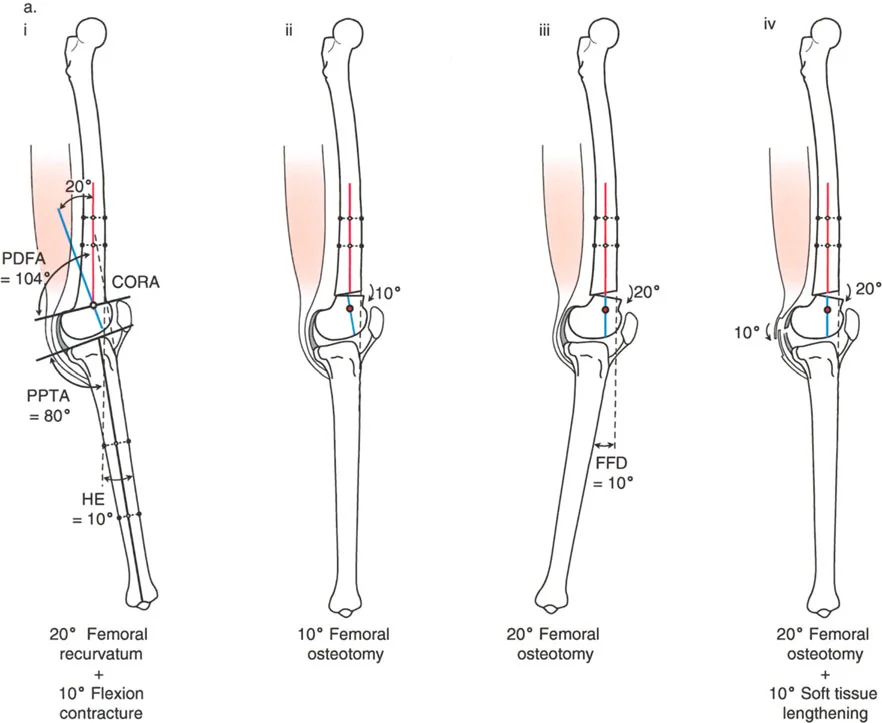

- على الرغم من أن الركبة الارتدادية هي فرط تمدد، إلا أنه في بعض الحالات، يمكن أن يترافق التشوه العظمي بتقلص في الأنسجة الرخوة يحد من انثناء الركبة. هذا التقلص يمكن أن "يخفي" أو "يعوض" جزئيًا فرط التمدد العظمي، مما يجعل الركبة تبدو في وضع تمدد طبيعي ظاهريًا.

- على سبيل المثال، إذا كان هناك ارتداد فخذي بمقدار 20 درجة مع تقلص انثناء 20 درجة، فقد تبدو الركبة في وضع تمدد كامل (0 درجة) ولكنها تعاني من فقدان في مدى الانثناء.

* قد لا يكون هناك فرط تمدد سريري واضح (HE = 0°)، لأن تقلص الانثناء يعوض التشوه العظمي.

* ومع ذلك، سيظل المريض يعاني من فقدان في مدى انثناء الركبة.

* في هذه الحالات، قد تكون الركبة "مستقرة" نسبيًا ولا تسبب أعراضًا شديدة إذا كانت غير مؤلمة.

- زاوية الانحناء البعيدة للفخذ (PDFA - Posterior Distal Femoral Angle): تقيس زاوية الجزء السفلي من عظم الفخذ. القيمة الطبيعية حوالي 84 درجة. الزيادة في هذه الزاوية (أكثر من 84 درجة) تشير إلى ارتداد فخذي.

- زاوية الانحناء القريبة للظنبوب (PPTA - Proximal Posterior Tibial Angle): تقيس زاوية الجزء العلوي من عظم الساق. القيمة الطبيعية حوالي 80 درجة. الزيادة في هذه الزاوية (أكثر من 80 درجة) تشير إلى ارتداد ظنبوبي.

- مركز دوران الزاوية (CORA - Center of Rotation of Angulation): يتم تحديد هذا النقطة على الأشعة السينية لتحديد مكان التشوه العظمي بدقة، وهو أمر بالغ الأهمية لتخطيط عملية قطع العظم.

- الركبة الارتدادية بسبب الارتداد الفخذي مع تقلص انثناء:

- إذا كان هناك ارتداد فخذي (PDFA > 84°) ولكن لا يوجد فرط تمدد سريري (HE = 0°)، فهذا يشير إلى وجود تقلص انثناء مصاحب يعوض التشوه العظمي.

- إذا كان فرط التمدد (HE) أقل من درجة الارتداد الفخذي، فهذا يعني وجود تقلص انثناء جزئي.

أ. قطع العظم الفخذي لتصحيح الارتداد الفخذي:

- متى يتم إجراؤها: عندما يكون التشوه الرئيسي في عظم الفخذ البعيد.

- الإجراء: يتم إجراء قطع للعظم (عادة قطع عظم انثناء) في الجزء البعيد من عظم الفخذ، عند مركز دوران الزاوية (CORA)، لإعادة محاذاة العظم.

- الهدف: تصحيح فرط تمدد الركبة واستعادة المحاذاة الطبيعية.

- مثال: لتصحيح ارتداد فخذي بمقدار 20 درجة، يتم إجراء قطع عظم انثناء فخذي بمقدار 20 درجة.